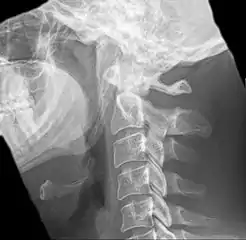

![]() | |

| Anteroposterior and lateral radiographs of cervical spine showing ossification of the stylohyoid ligament on both sides | |